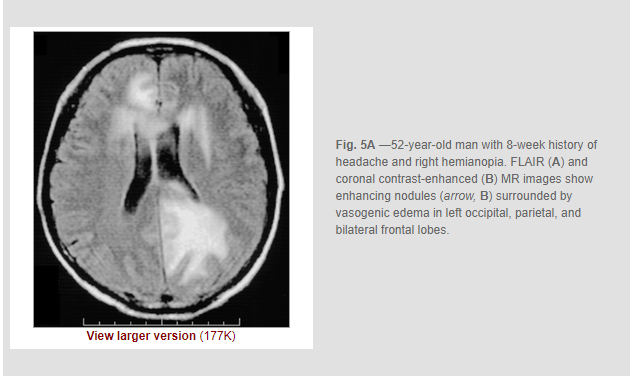

Liu H, Lim CC, Feng X, Yao Z, Chen Y, Sun H, Chen X. MRI in cerebral schistosomiasis: characteristic nodular enhancement in 33 patients. AJR Am J Roentgenol. 2008 Aug;191(2):582-8. doi: 10.2214/AJR.07.3139. PMID: 18647936.

Objective: The purpose of our study was to describe the characteristic MRI appearance of cerebral infection with Schistosoma japonicum.

Conclusion: Cerebral infection with S. japonicum can cause a characteristic MRI pattern of a large mass comprising multiple intensely enhancing nodules, sometimes with areas of linear enhancement. The typical appearance may be useful for diagnosis in endemic regions and may potentially be useful in cases imported into countries in which the disease is not endemic.